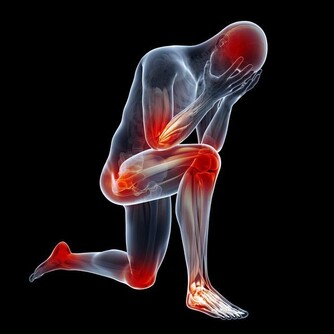

1. 止咳化痰

咳嗽是秋天高發病,一旦得上就很難好,用艾葉泡腳,每天20分鐘,泡第一次就會有改善,並且還能清肺熱,排肺毒。